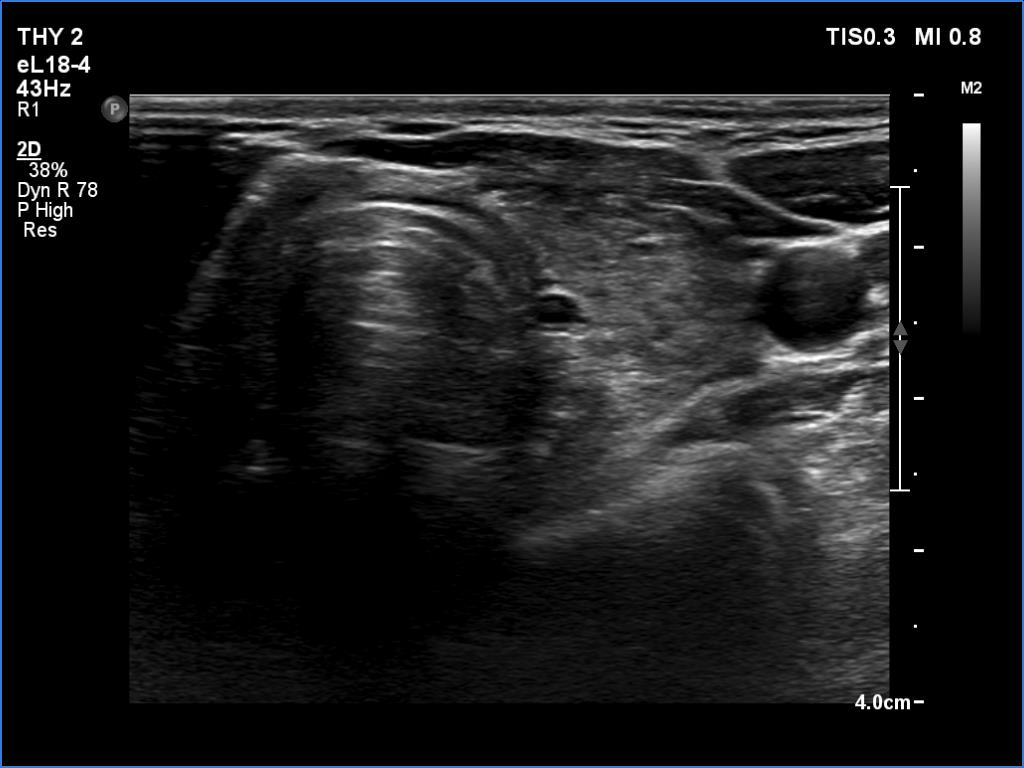

Ultrasonography. The thyroid was hypoechoic and presented several more hypoechoic and echonormal islets corresponding to the underlying thyroiditis. There was a mixed, dominantly cystic mass dorsal to the lower two-third of the right lobe. The lesion has echonormal solid part and showed intracystic echogenic figures.